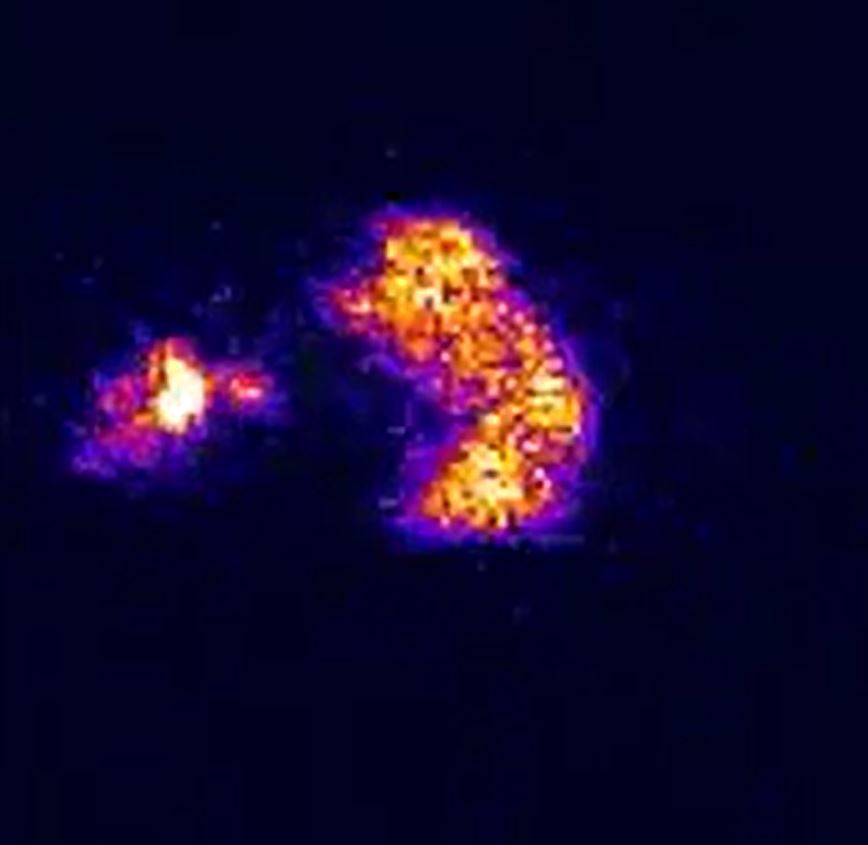

Q

Is this normal?

A

Yes.. this is 99mTc Mebrofenin.. where, in a normal study, all the Tc goes to the liver and stays there.